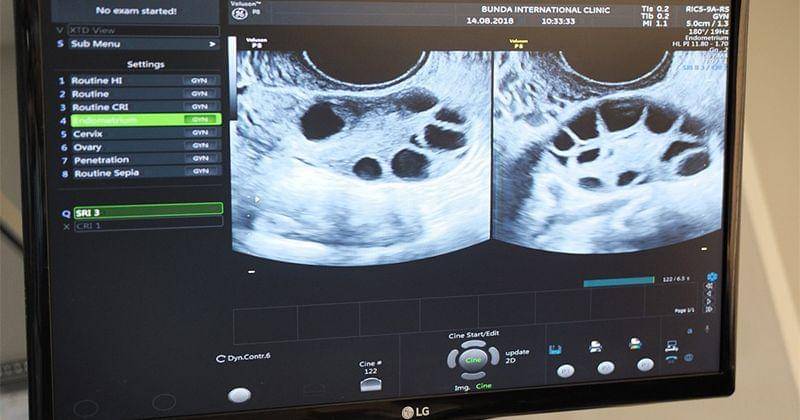

Untuk beberapa orang yang belum mengenal proses IVF ini, mungkin merasa bingung dengan banyaknya lubang-lubang pada monitor USG. Lubang-lubang yang terlihat pada foto ini merupakan sel telur dari Tya Ariestya.

Ada 17 sel telur yang merespon baik terhadap obat stimulasinya. Ada 10 sel telur di kanan dan 7 sel telur lainnya di sebelah kiri.